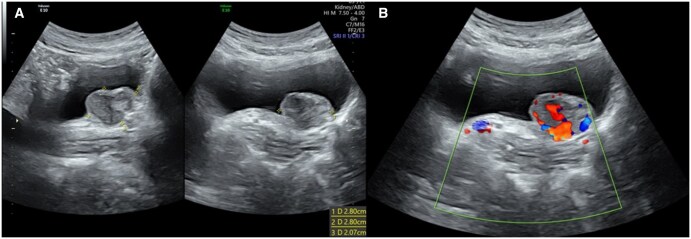

Paragangliomas (PGLs) during pregnancy is an uncommon neuroendocrine tumour that is associated with increased maternal and foetal morbidity and mortality. Furthermore, it is even rarer for these to be located within the urinary bladder, with a prevalence of <0.1% of all bladder tumours. This case report details a 29-year-old female who presented with pre-syncope, headache, and palpitations during voiding. Ultrasound and magnetic resonance imaging of the pelvis revealed a mass in her bladder, and biochemical workup demonstrated elevated plasma normetanephrine levels and a positive clonidine suppression test. Surgical resection and histopathology of the mass were consistent with PGL. Post-operatively, the patient was normotensive, her normetadrenaline levels normalized and she was discharged 3 days after the operation. She progressed through the remaining pregnancy without any significant complications and delivered a healthy baby at full term. This case depicts the rare nature of PGLs in pregnancy and the importance of antenatal imaging combined with a multidisciplinary approach for a successful pregnancy outcome.

Abstract Image